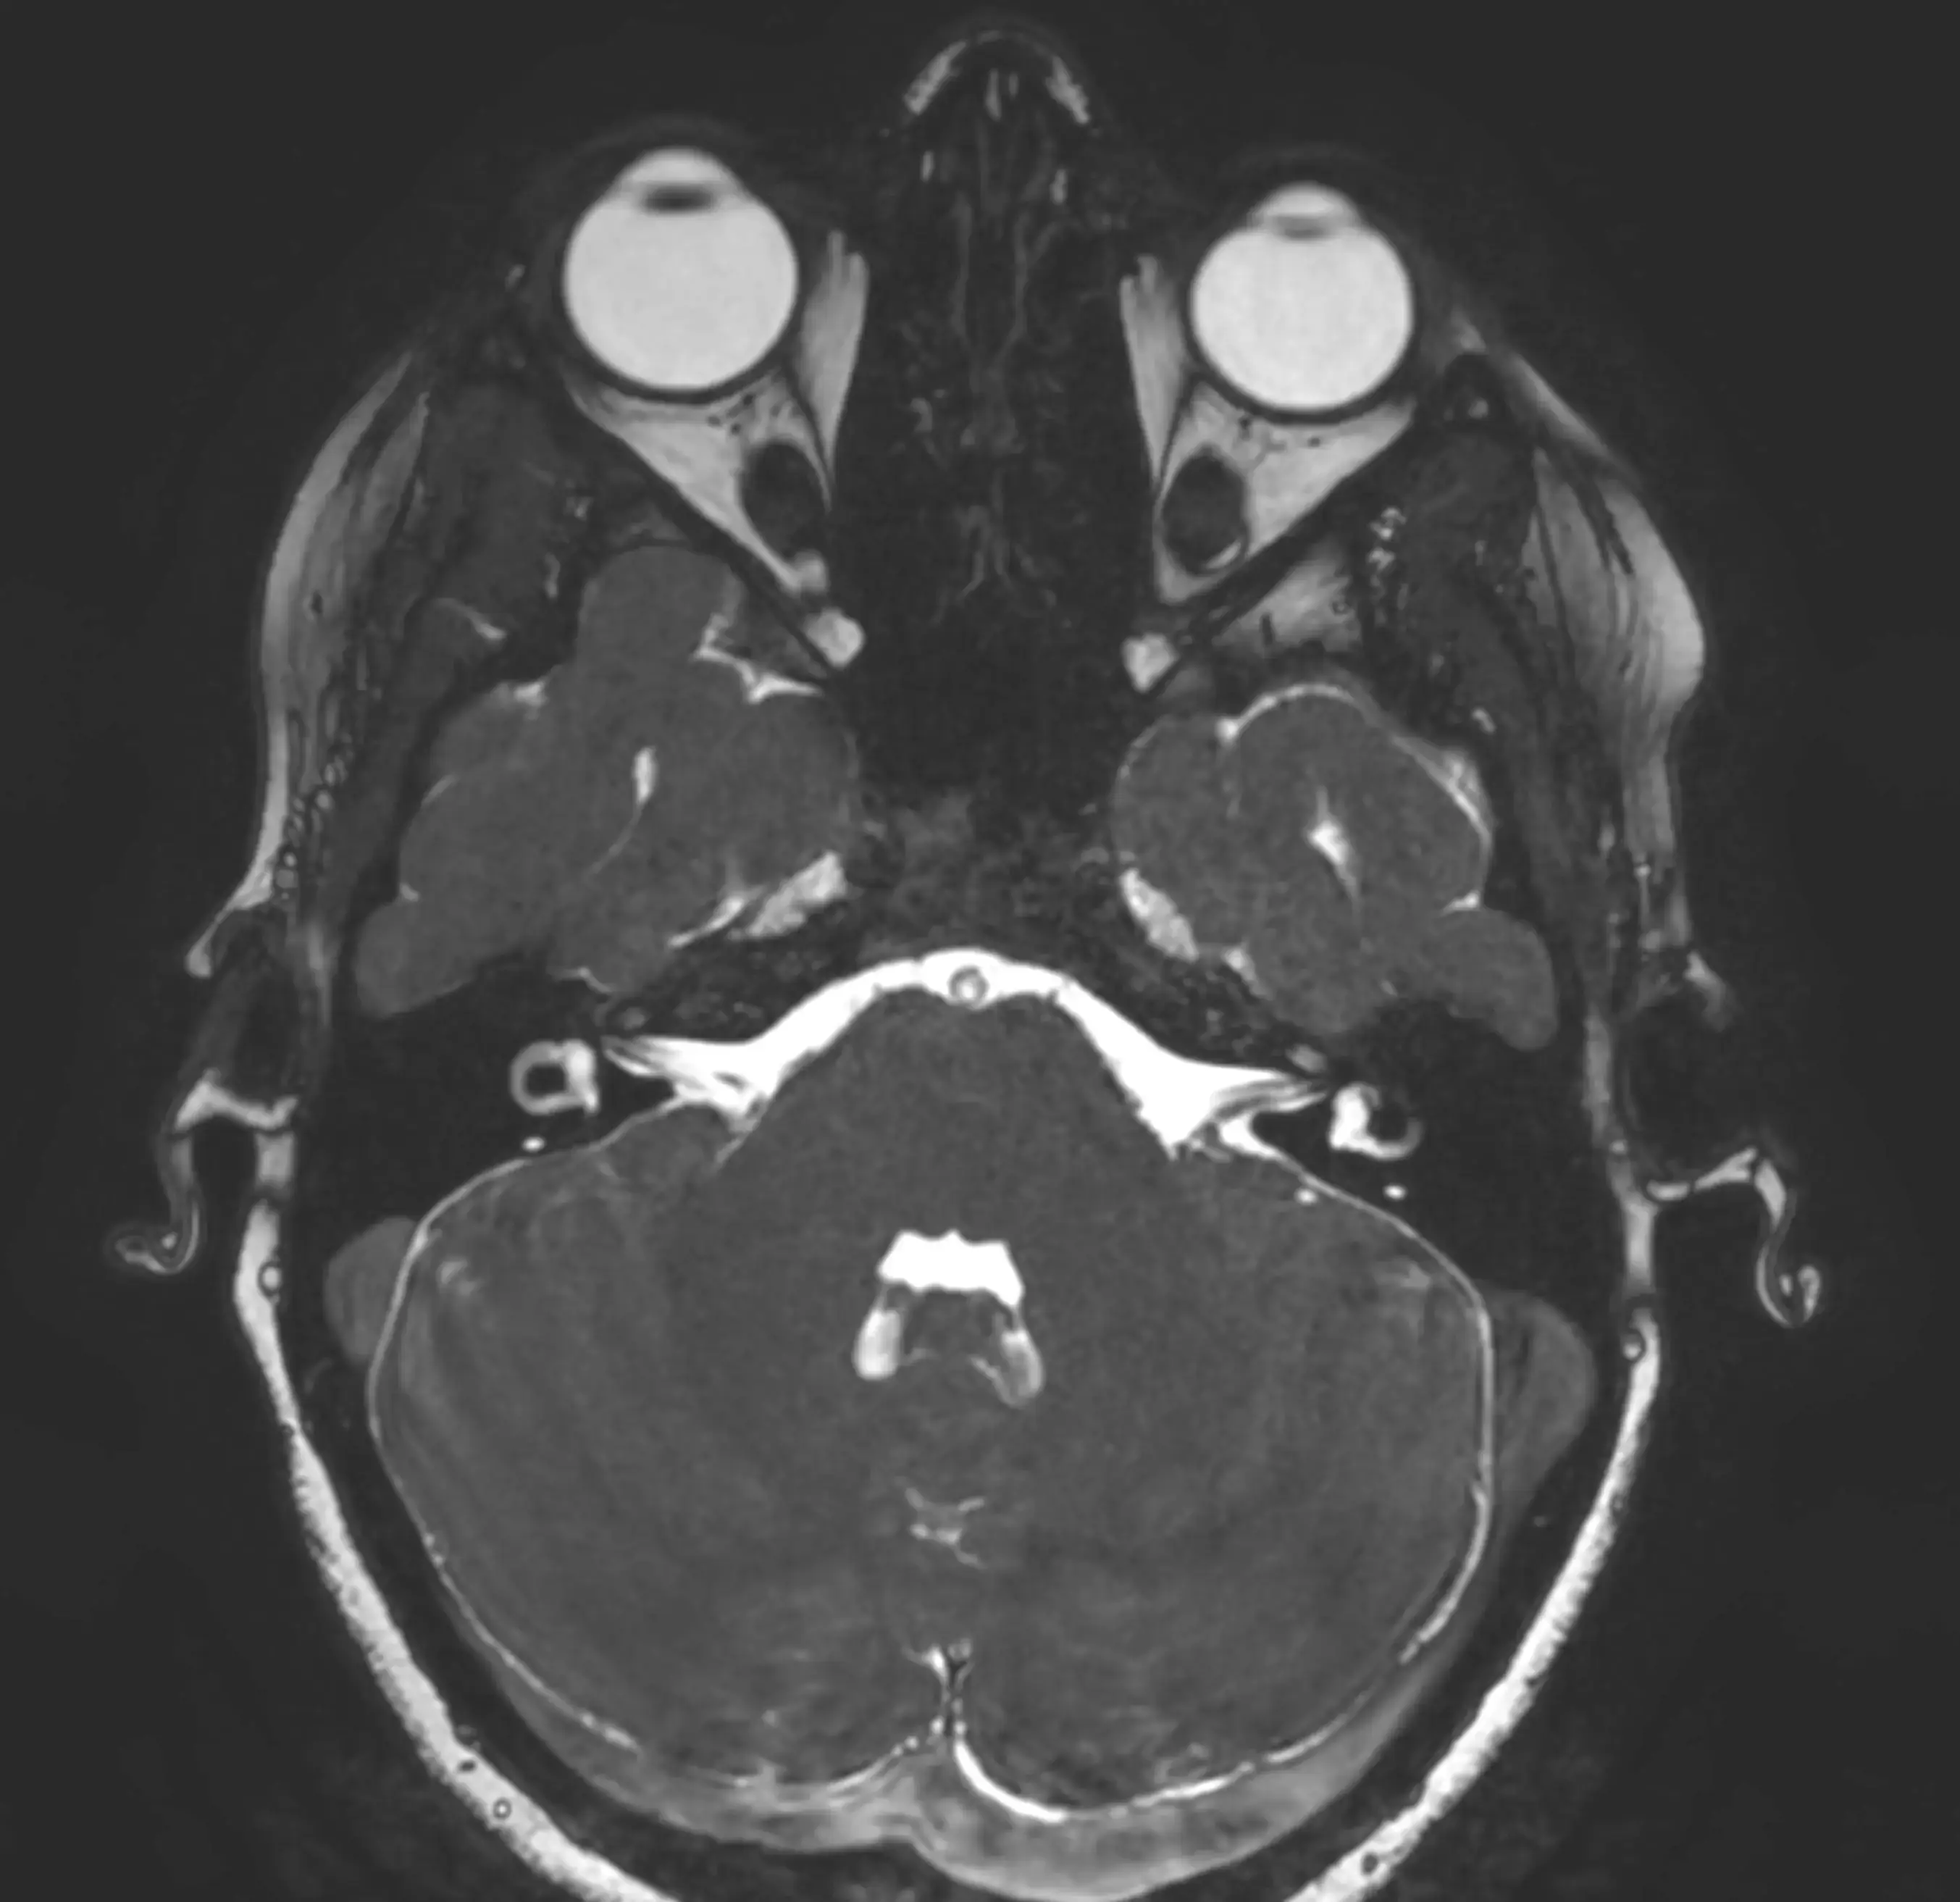

МРТ ока і очних орбіт — це сучасний метод обстеження, який дозволяє детально оцінити стан очних яблук, зорових нервів, м’язів ока та тканин очниці.

Магнітно-резонансна томографія дає можливість отримати високоточні зображення без використання рентгенівського випромінювання, що робить дослідження безпечним для пацієнтів.

Що показує МРТ очних орбіт

Дослідження дозволяє виявити:

- пухлини очної орбіти

- запальні процеси

- патології зорового нерва

- травматичні ушкодження

- зміни очних м’язів

- судинні порушення

- вроджені аномалії